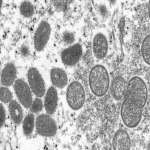

السودان يعلن تسجيل أول حالة مؤكدة بجدري القرود أعلنت وزارة الصحة السودانية، اليوم، عن تسجيل أول حالة مؤكدة بجدري القرود بولاية غرب دارفور لطالب.واو...